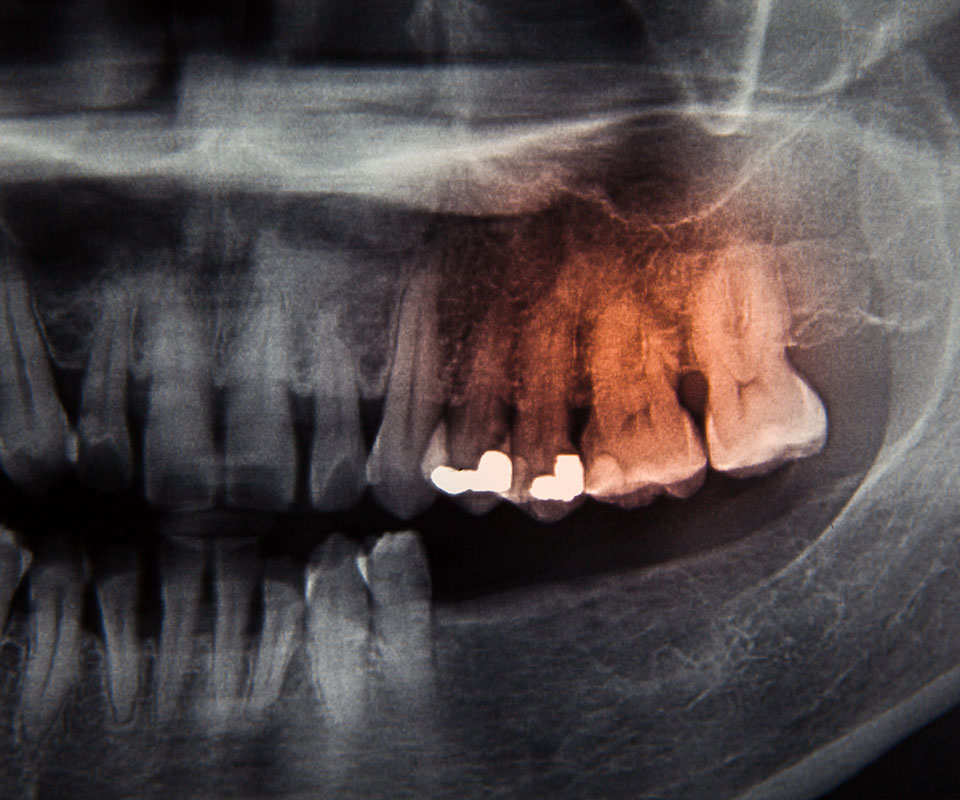

Simply put, oral cancer screening is an examination performed by one of our experienced dentists here at Empress Walk Dental. The doctor checks for signs of oral cancer or even precancerous conditions. The primary goal of our oral cancer screening is to help our patients identify mouth cancer early enough and boost their chances of fighting it successfully. At Empress Walk Dental, we recommend routine visits to our clinics and get screened for oral cancer. Sometimes, our dentists might perform additional tests to help identify areas of abnormal cell growth in your mouth. If the symptoms of this health condition are recognized during your annual oral cancer examination, the condition can be handled effectively, especially during the early stages.

Typically, oral cancer screening is a simple, non-invasive, and painless procedure. At Empress Walk Dental, your dentist will examine your glands, mouth, face, and neck for any physical signs such as lumps, leukoplakia, red patches, and sores.

In case you have these symptoms, the dentist will implement a diagnostic and treatment plan immediately. Sometimes a biopsy may be necessary to establish the right stage of cancer and determine whether or not it is posing secondary threats to your dental health.